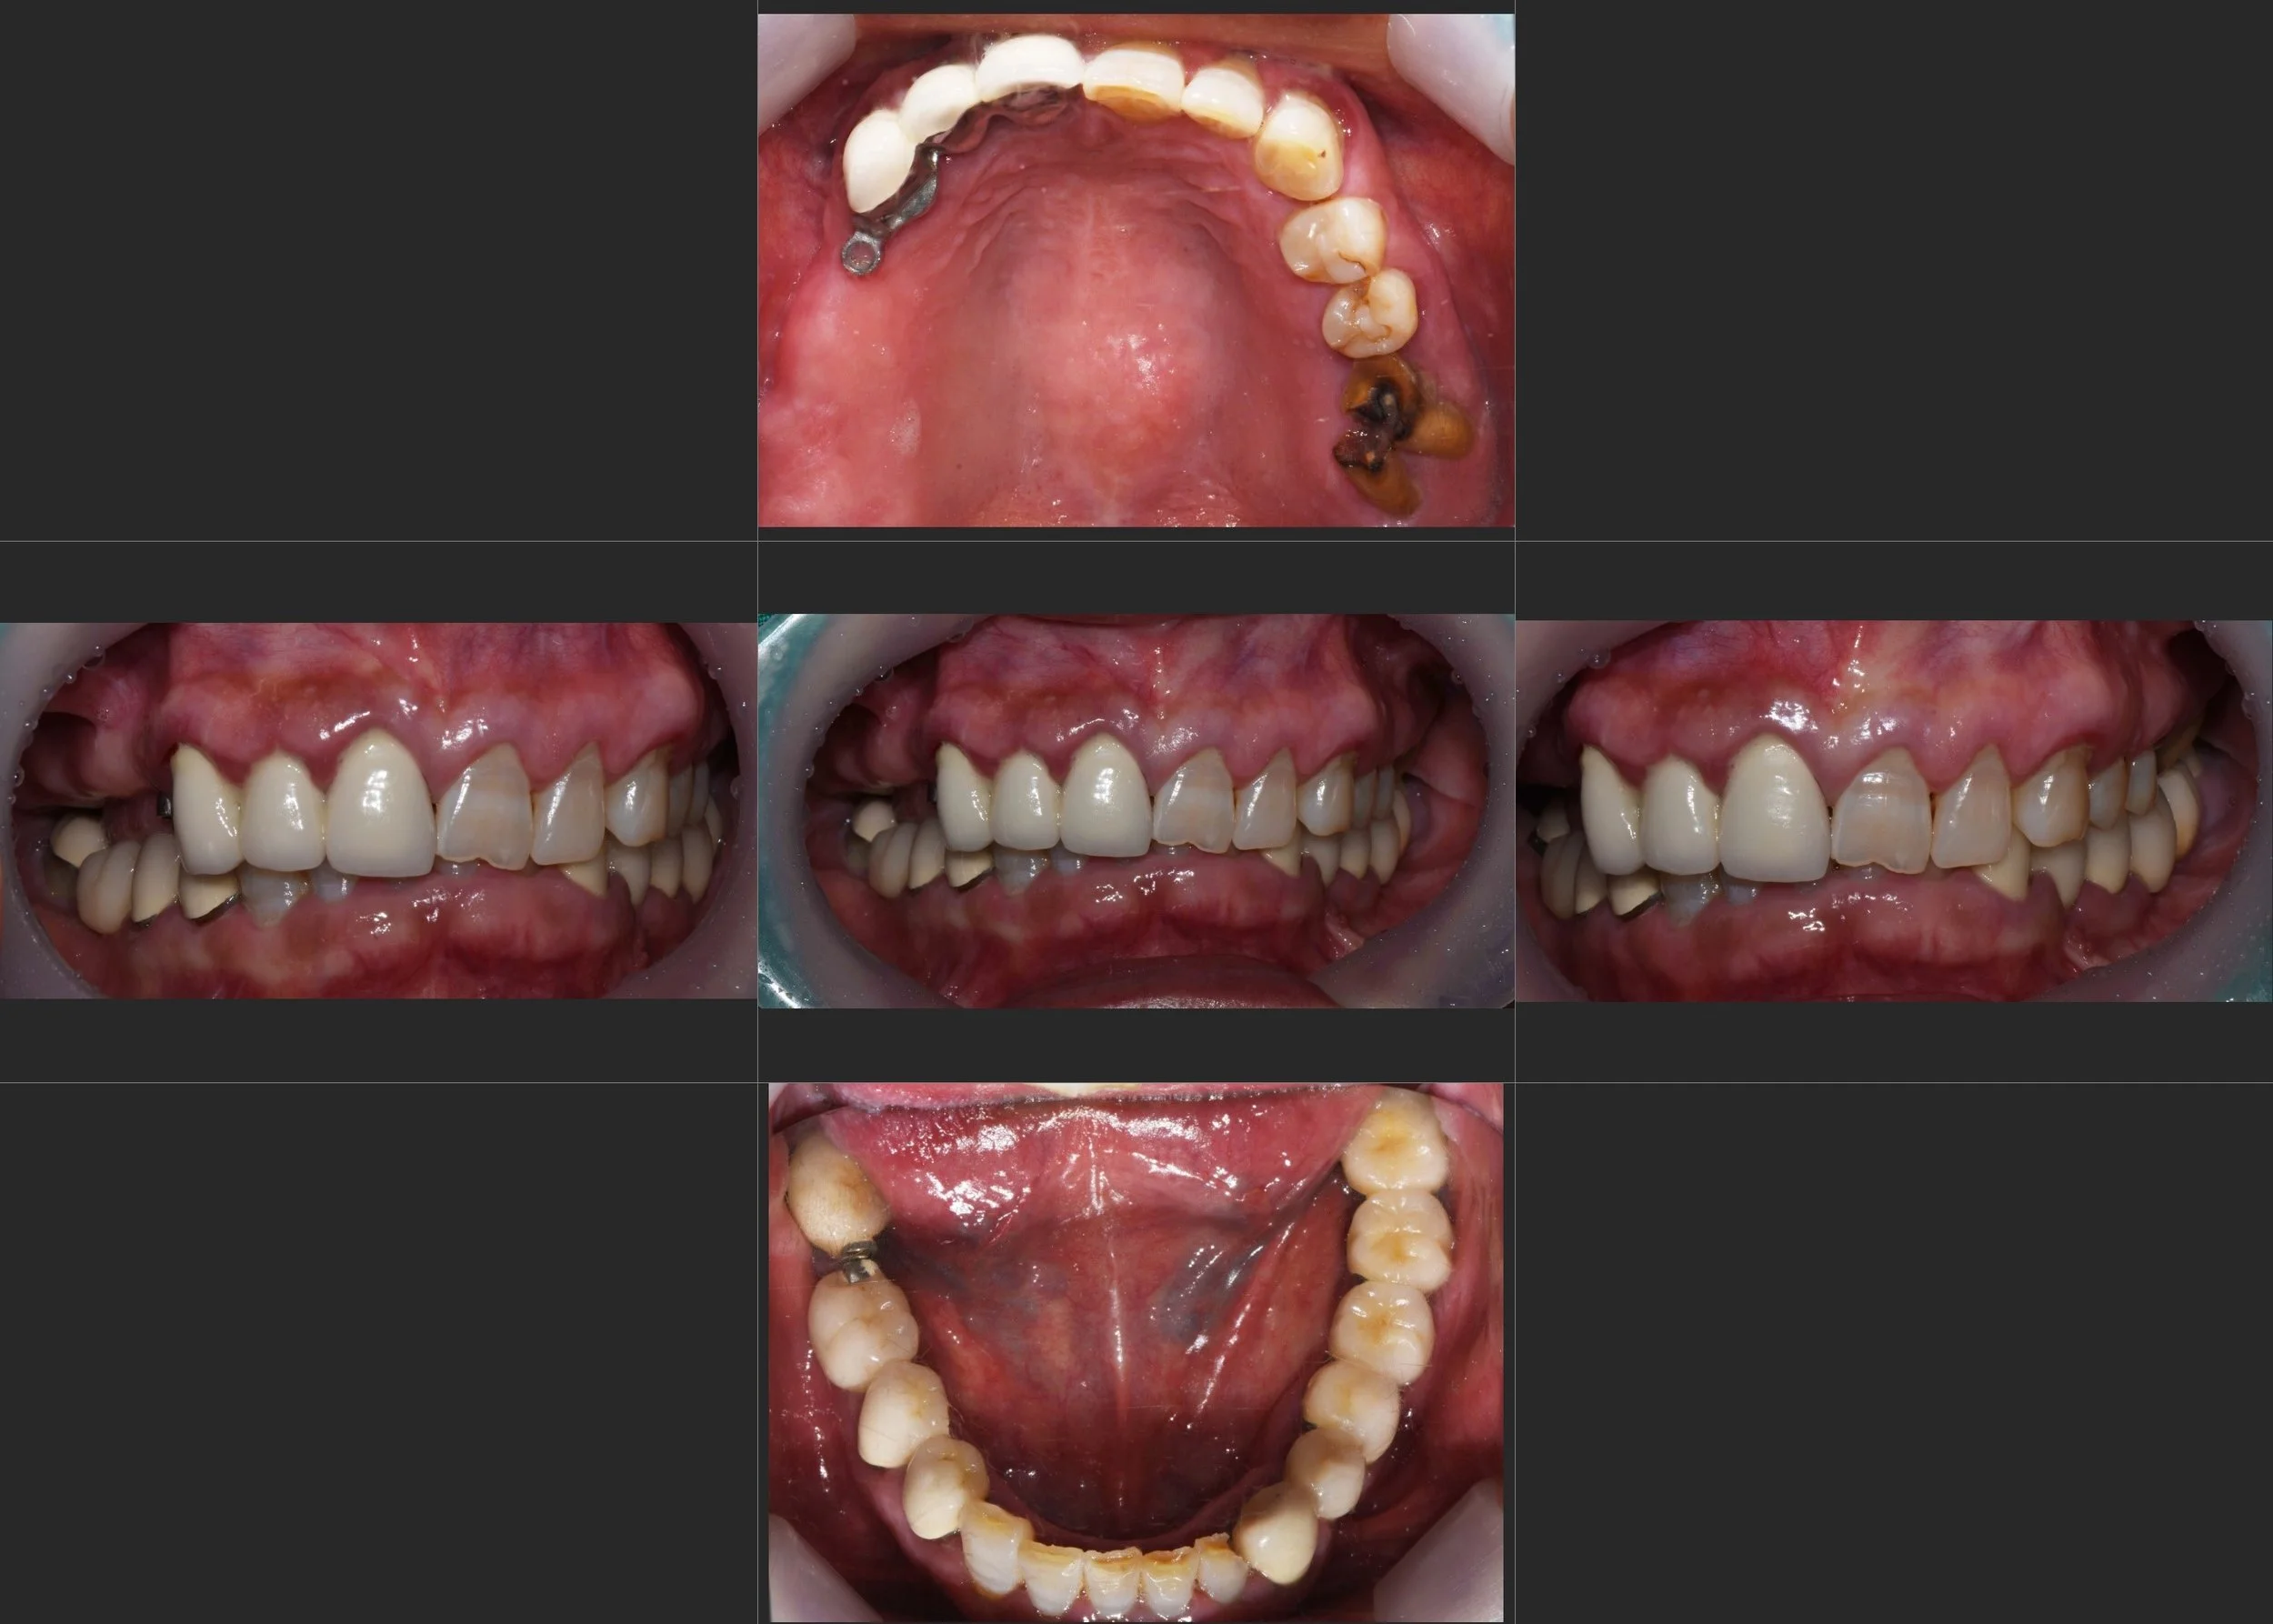

35. Comprehensive Full-Arch Transformation: Restoring Confidence in a Young Phobic Patient

Reversing the effects of generalized rampant caries and occlusal collapse in a female patient in her 20s. A tooth-preserving, implant-assisted approach focused on stable VDO elevation and overcoming social anxiety.